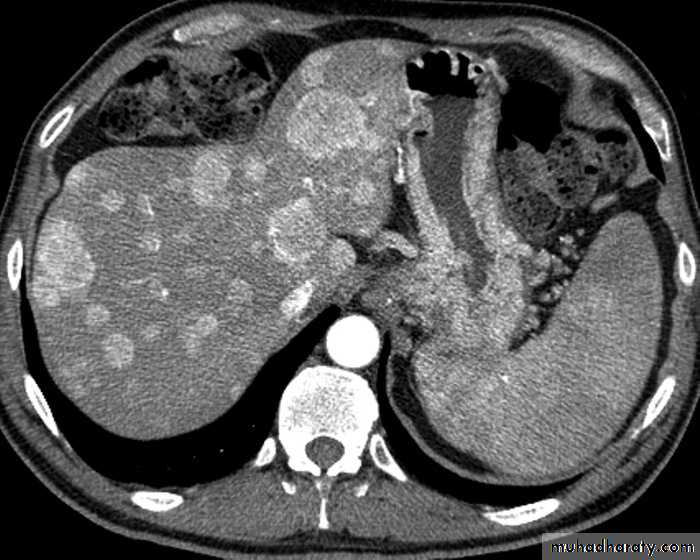

CT scan

Malignant neoplasms:

hepatocellular carcinoma